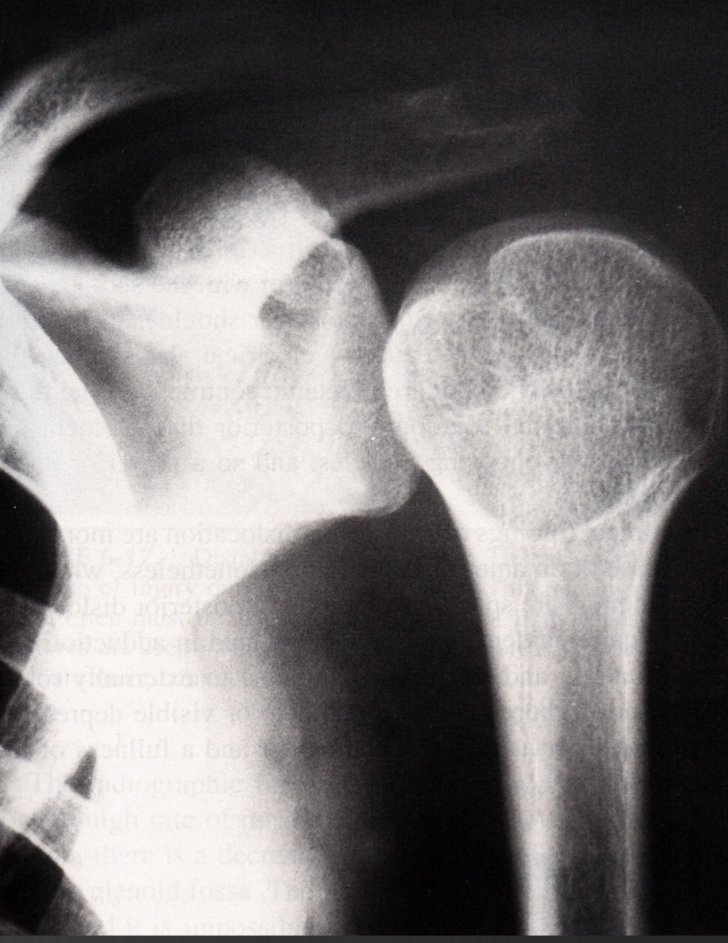

ice cream on a cond lightbulb on a stick is a comon discription of

posterior dislocation in AP view

axial view of posterior humeral head is oppostie to the corocoid process

normal axial

anterior dislocation axial

humeral head overlaps coracoid